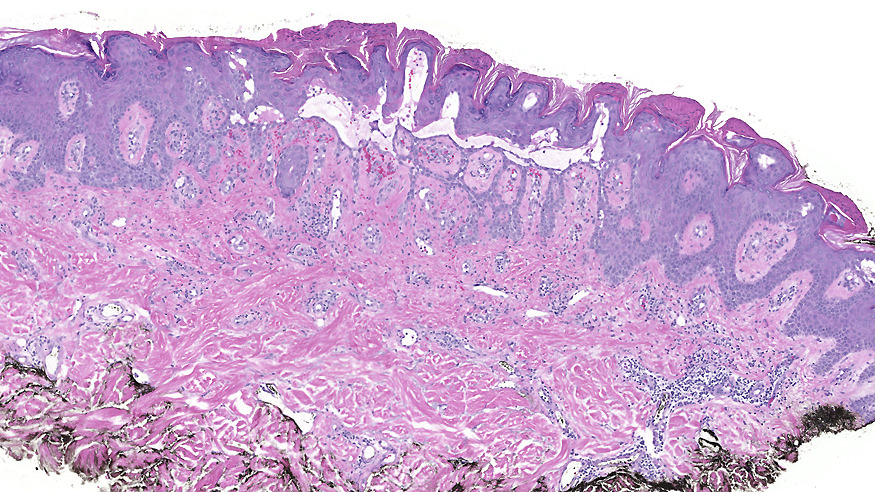

Microscopic (histologic) description

- Suprabasal acantholysis with vesicle formation is the principal microscopic finding

- Elongation of rete ridges with focal acantholysis and eosinophils may be the only early changes in Grover disease

- Main 4 histopathological patterns are:

- Pemphigus vulgaris / foliaceous-like: predominantly limited to suprabasal acantholysis, with basal keratinocytes attached to basement membrane forming a characteristic tombstone appearance

- Darier-like: suprabasal acantholysis of keratinocytes with scattered apoptotic or dyskeratotic cells within various levels of the epidermis

- Spongiotic: edema within epidermis, causing separation of keratinocytes and prominent intracellular bridges

- Hailey-Hailey-like: suprabasal acantholysis of all levels of the epidermis without significant dyskeratosis (dilapidated brick wall appearance)

- More than one pattern can be seen in the same setting

- Other newly described histopathological pattern include: (Am J Dermatopathol 2010;32:541)

- Porokeratotic: presence of oblique columns of parakeratosis over areas of epidermis devoid of granular layer, with occasional dyskeratotic cells in the upper epidermal layers and a tendency to basal vacuolization

- Lentiginous: elongation of the rete ridges with some basal hyperpigmentation resembling a solar lentigo or Dowling-Degos disease

- Vesicular: intraepidermal vesicles with minimal spongiosis or acantholysis on their sides

- Lichenoid: vacuolar damage and slight lymphocytic infiltrate at the dermoepidermal junction, with occasional dyskeratosis and barely identifiable acantholysis

- Dysmaturative: disordered keratinocyte maturation with nuclear pleomorphism and slight hyperchromasia (Am J Dermatopathol 2018;40:642)

- Epidermolytic hyperkeratosis-like pattern (Am J Dermatopathol 2014;36:358)

Microscopic (histologic) images